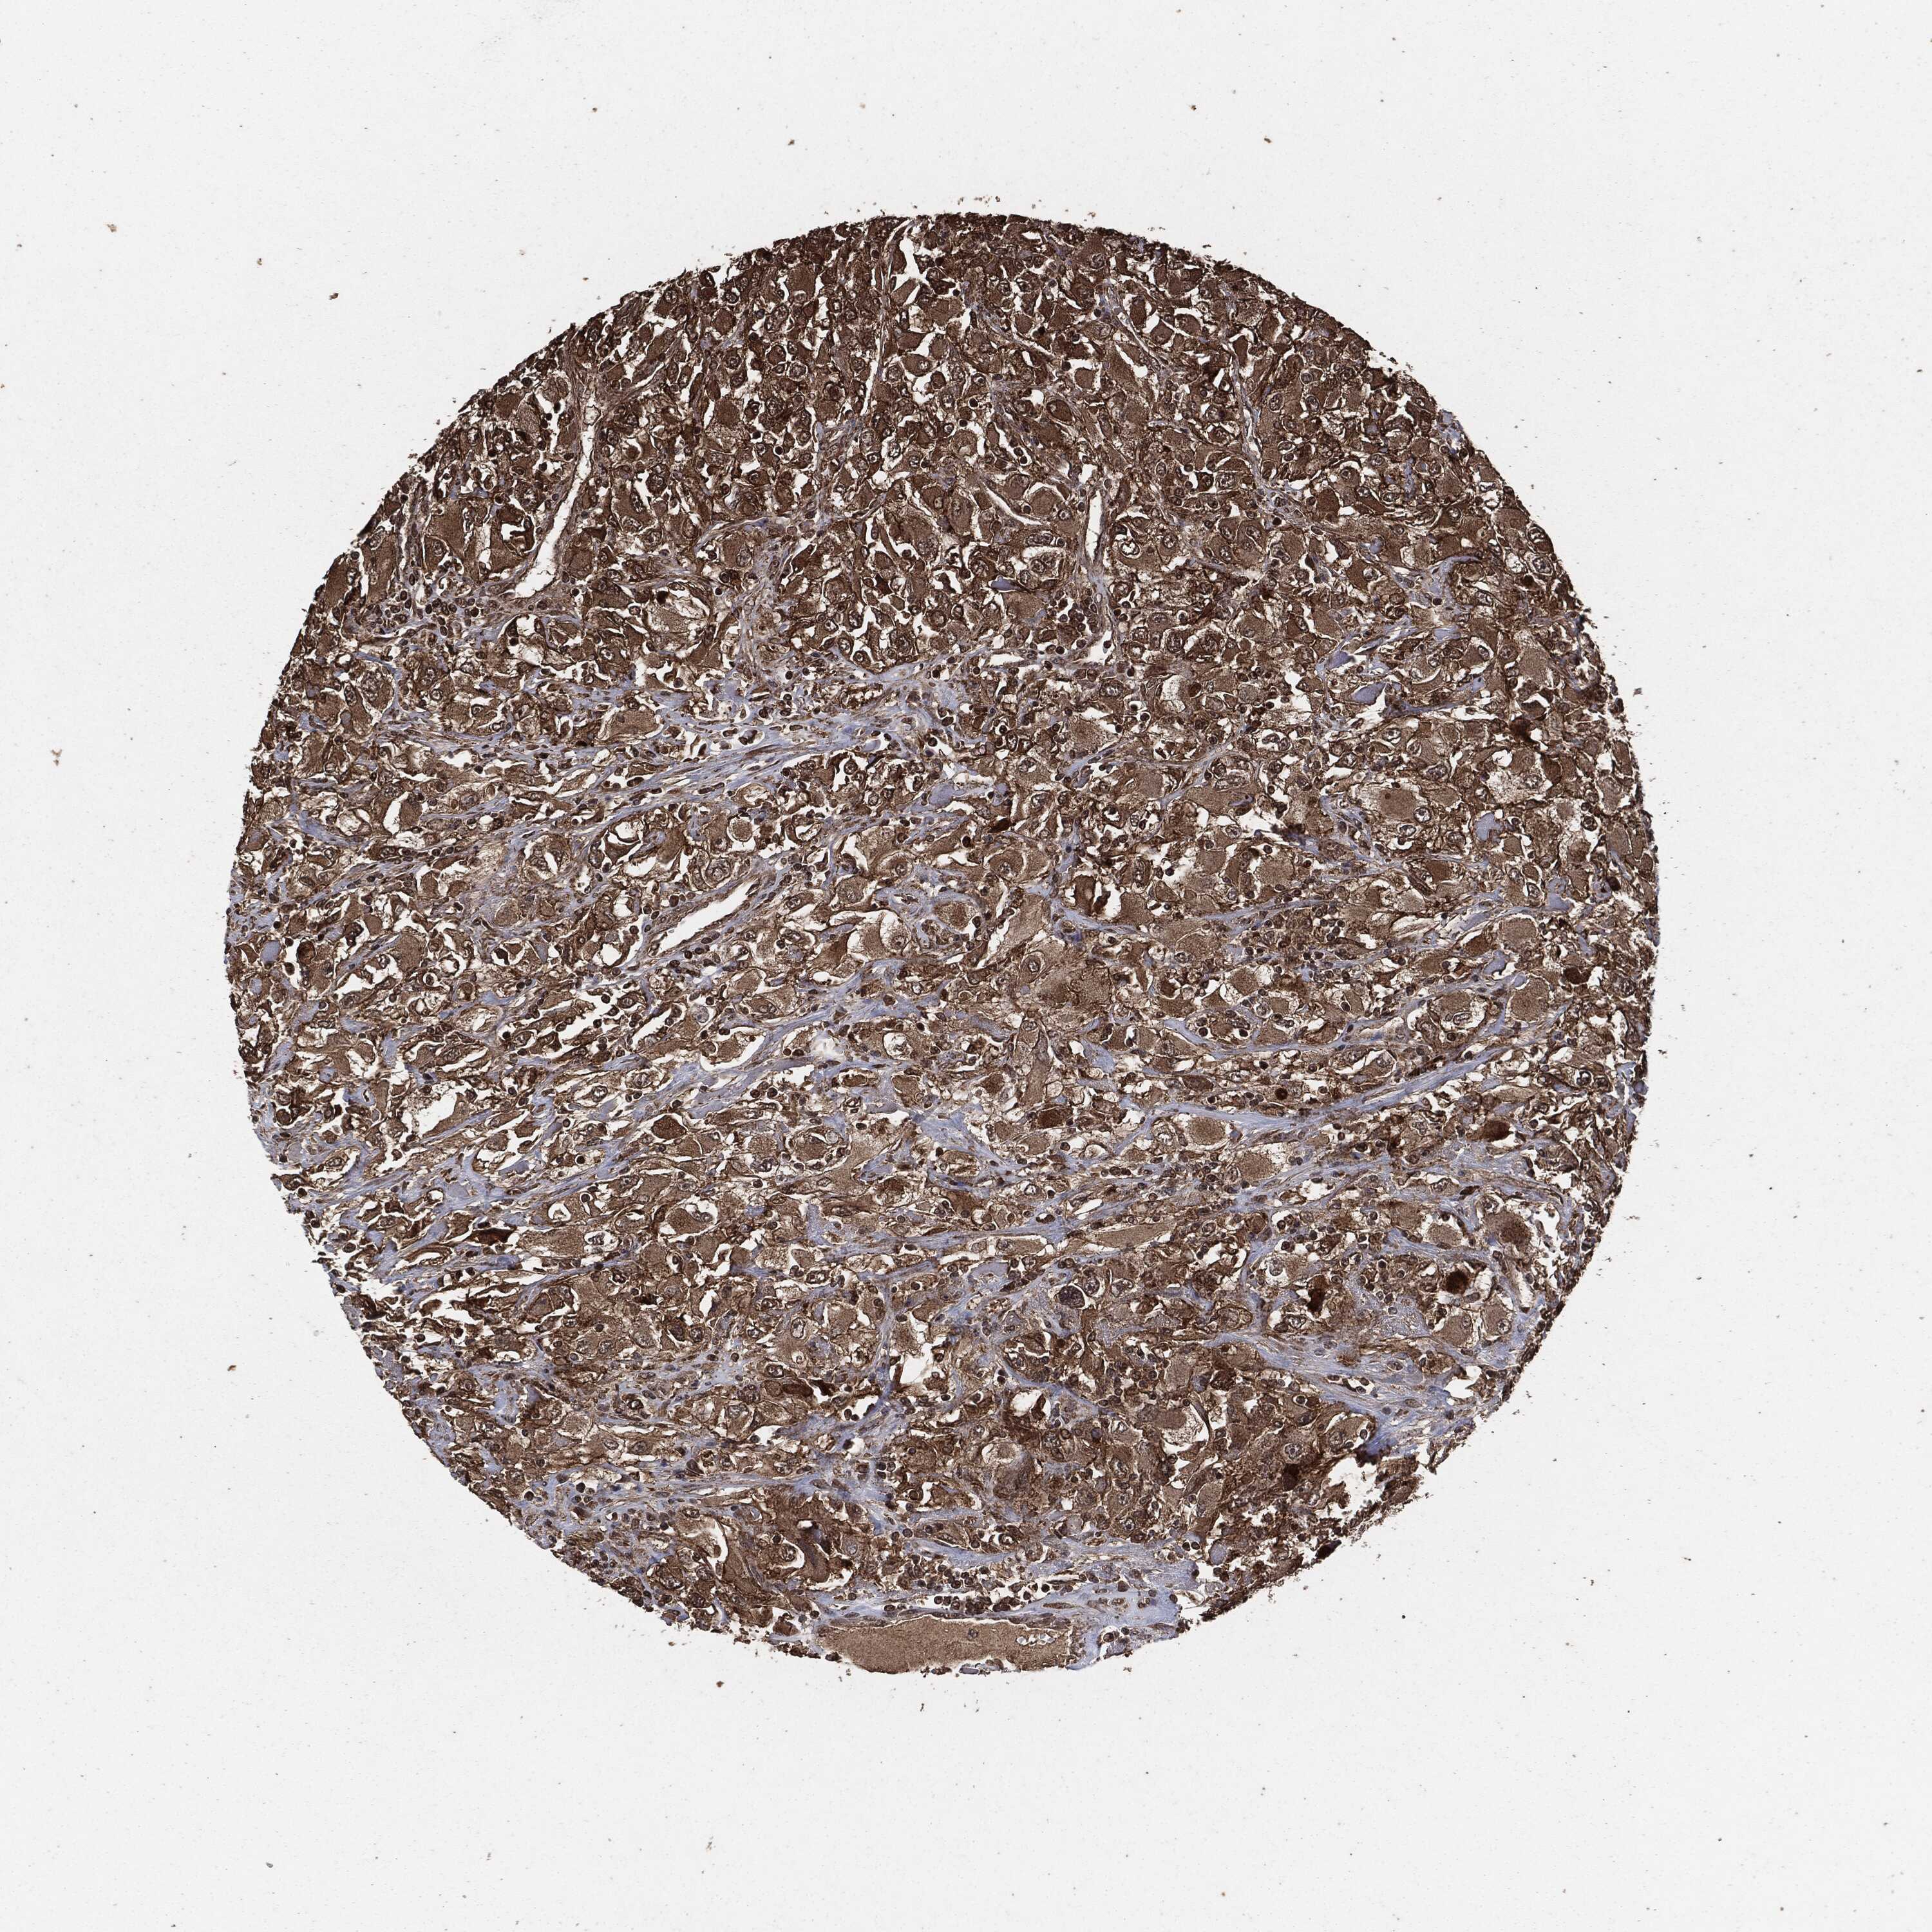

KIDNEY RENAL CLEAR CELL CARCINOMA (VALIDATION) - Interactive survival scatter ploti

The Survival Scatter plot shows the clinical status (i.e. dead or alive) for all individuals in the patient cohort, based on the same data that underlies the corresponding Kaplan-Meier plots. Patients that are alive at last time for follow-up are shown in blue and patients who have died during the study are shown in red.

The x-axis shows the expression levels (FPKM) of the investigated gene in the tumor tissue at the time of diagnosis. The y-axis shows the follow-up time after diagnosis (years). Both axes are complimented with kernel density curves demonstrating the data density over the axes. The top density plot shows the expression levels (FPKM) distribution among dead (red) and alive patients (blue). The right density plot shows the data density of the survived years of dead patients with high and low expression levels respectively, stratified using the cutoff indicated by the vertical dashed line through the Survival Scatter plot. This cutoff is automatically defined based on the FPKM cutoff that minimizes the p-score. The cutoff can be changed by dragging the vertical line or by entering a cutoff value in the square labeled "Current cut-off".

Under the Survival Scatter plot the p-score landscape (black curve; left axis) is shown together with dead median separation (red curve; right axis). Dead median separation is the difference in median mRNA expression between patients who have died with high and low expression, respectively. It is calculated as follows: median FPKM expression of dead patients with high expression - median FPKM expression of dead patients with low expression. This is intended to aid the user in visually exploring custom cutoffs and the associated p-scores and dead median separation.

Individual patient data is displayed and can be filtered by clicking on one or more of the category buttons on the top of the page. Categories describing expression level and patient information include: high, low, alive, dead, female, male and tumor stages. The scale of the x-axis can be toggled between linear and log-scale by clicking on the "x log" button. Mouse-over function shows TCGA ID, patient information and mRNA expression (FPKM) for each patient.

& Survival analysisi

Kaplan-Meier plots summarize results from analysis of correlation between mRNA expression level and patient survival. Patients were divided based on level of expression into one of the two groups "low" (under cut off) or "high" (over cut off). X-axis shows time for survival (years) and y-axis shows the probability of survival, where 1.0 corresponds to 100 percent.

EGFR is not prognostic in Kidney Renal Clear Cell Carcinoma (validation)

Best expression cut offi

Based on the FPKM value of each gene, patients were classified into two groups and association between prognosis (survival) and gene expression (FPKM) was examined. The best expression cut-off refers the FPKM value that yields maximal difference with regard to survival between the two groups at the lowest log-rank P-value. Best expression cut-off was selected based on survival analysis .

When clicking on this number, the vertical dashed line indicating cut-off, the interactive survival plot, and the Kaplan-Meier curve will be adjusted to show results based on the best expression cut-off.

: 44.55

Median expressioni

Median expression refers to the median FPKM value calculated based on the gene expression (FPKM) data from all patients in this dataset. When clicking on this number, the vertical dashed line indicating cut-off, the interactive survival plot, and the Kaplan-Meier curve will be adjusted to show results based on the median expression.

: N/A

Median follow up timei

Median follow up time refers to the median time (years) after diagnosis with this type of cancer, based on clinical data from all patients in this dataset.

P scorei

Log-rank P value for Kaplan-Meier plot showing results from analysis of correlation between mRNA expression level and patient survival.

N/A

5-year survival highi

5-year survival for patients with higher expression than the expression cutoff.

For melanoma and glioma, 3-year survival is shown.

5-year survival lowi

5-year survival for patients with lower expression than the expression cutoff.

TCGA RNA samplesi

RNA-seq data is reported as average FPKM (number Fragments Per Kilobase of exon per Million reads), generated by the The Cancer Genome Atlas (TCGA) .

Normal distribution across the dataset is visualized with box plots, shown as median and 25th and 75th percentiles. Points are displayed as outliers if they are above or below 1.5 times the interquartile range. FPKM values of the individual samples are presented next to the box plot.

Average pTPM 89.3

Number of samples 100